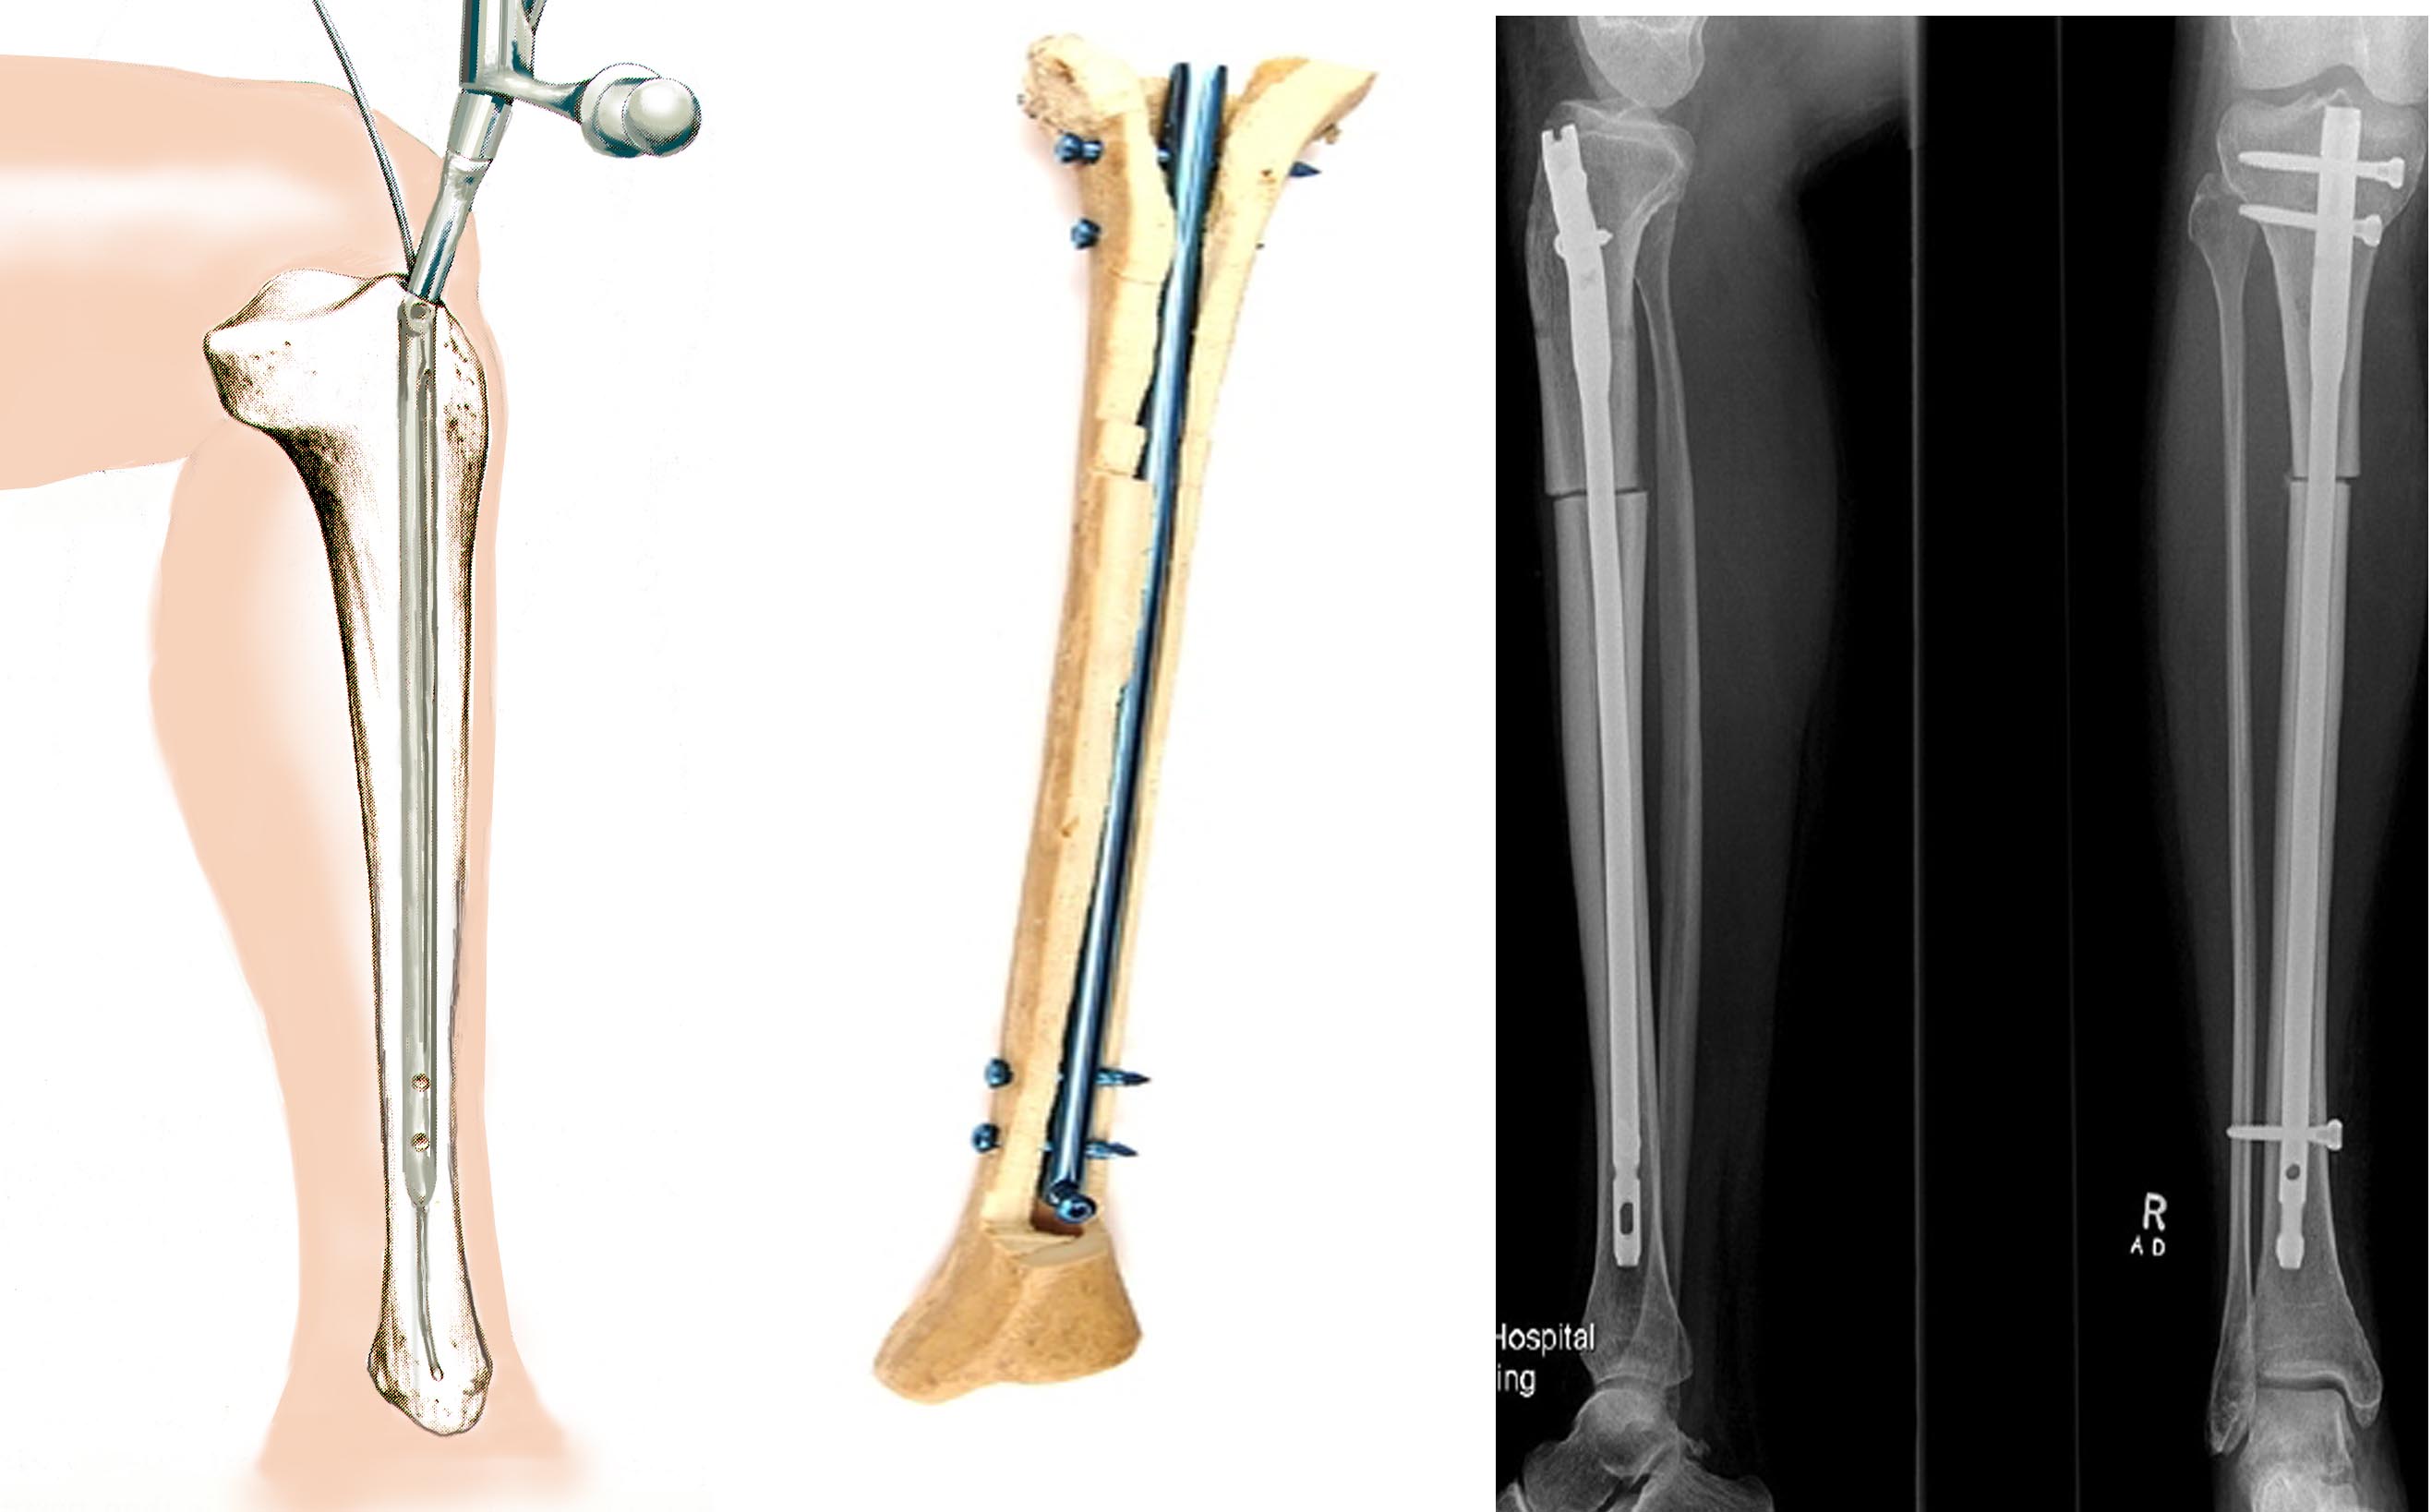

Интрамедуллярный остеосинтез

Большеберцовая кость рентген

Здесь представлены медицинские изображения переломов большой берцовой кости, сделанные врачами в процессе диагностики и лечения. Вы сможете увидеть, как выглядит этот тип травмы на рентгеновских снимках и других медицинских изображениях.